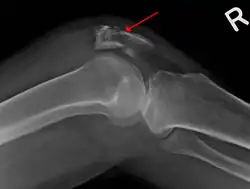

Some people have a normal bipartite patella or two-part patella which can appear as a fracture. The fragment is usually seen in the top outer corner of the patella and can be distinguished from a fracture by being present in both knees.[6]